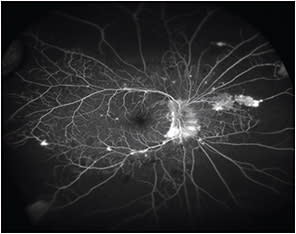

One of the most interesting observations from the ability to perform UWF FA is the realization that there exists considerable nonperfusion in the peripheral retina among eyes with retinal vascular diseases, including diabetic retinopathy and RVO (Figure 2).

Figure 2. Ultrawidefield fluorescein angiogram of a patient with proliferative diabetic retinopathy. Several areas of leakage from new vessels are seen. There is also extensive peripheral retinal nonperfusion.